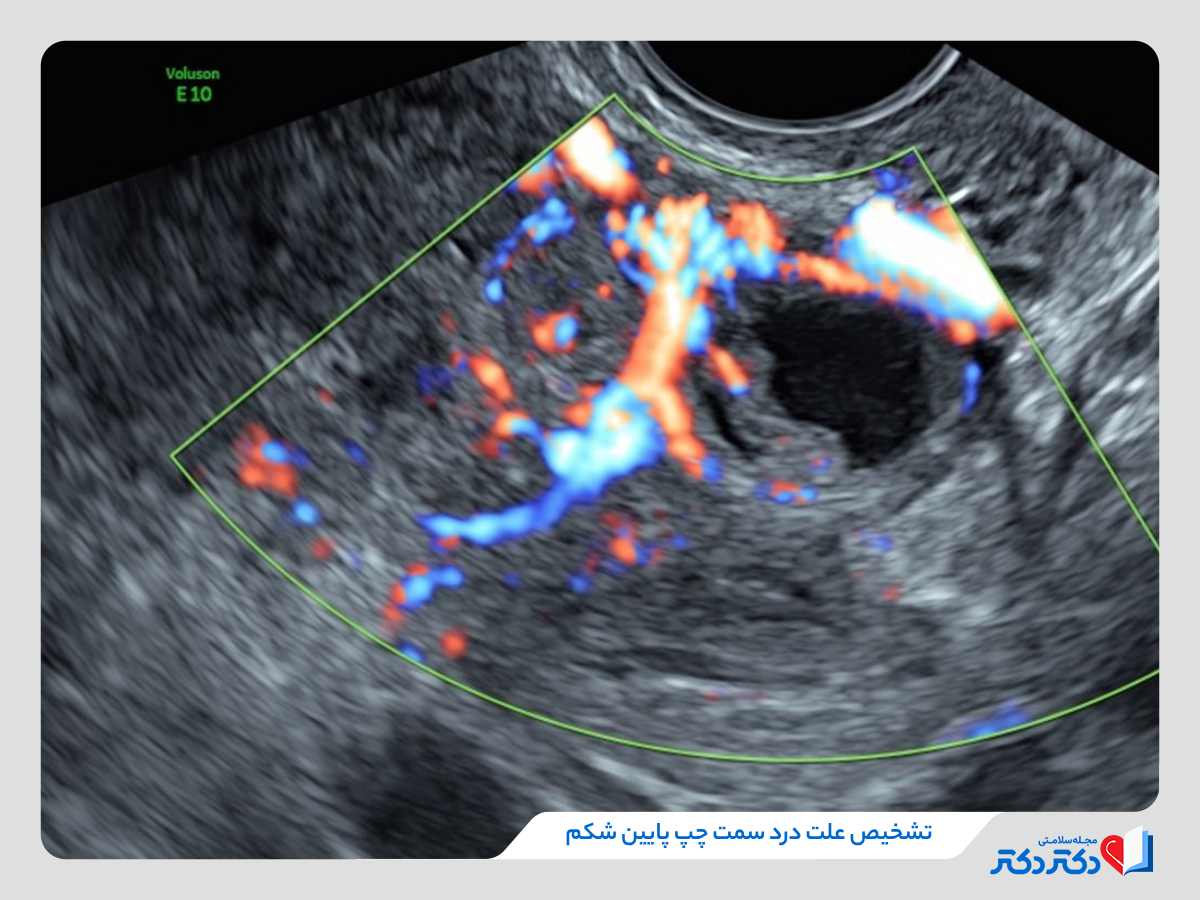

تشخیص درد شکم در سمت چپ پایین

علاوه بر معاینه فیزیکی در زمان مراجعه به پزشک برای درمان درد، امکان پذیر برای تشخیص دقیقتر و ریشهیابی درد آزمایشهای فرد دیگر نیز انجام دهید از جمله:

- سونوگرافی